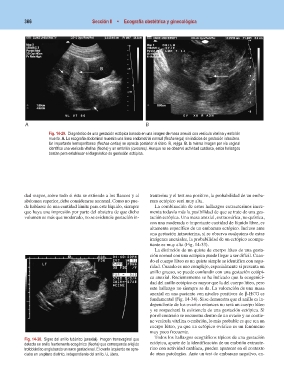

Fig. 14-29. Diagnóstico de una gestación ectópica basado en una imagen de masa anexial con vesícula vitelina y embrión

muerto. A. La ecografía abdominal muestra una línea endometrial normal (flecha larga) sin indicios de gestación intraútero.

Un importante hemoperitoneo (flechas cortas) se aprecia posterior al útero. B, vejiga. B. la misma imagen por vía vaginal

identifica una vesícula vitelina (flecha) y un embrión (cursores). Aunque no se observó actividad cardíaca, estos hallazgos

bastan para establecer el diagnóstico de gestación ectópica.